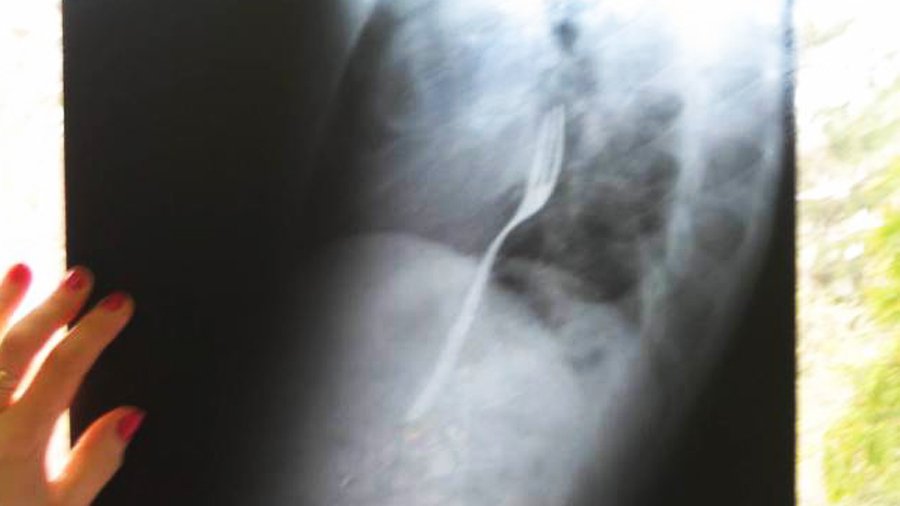

Врачи из румынского города Бакэу были шокированы, обнаружив в желудке у мужчины, обратившегося к ним за помощью, металлическую вилку.::: Выяснилось, что 25-летний Раду Калинцеску проглотил столовый прибор на спор. Молодому человеку хотелось произвести впечатление на друга, сообщает Metro.

Молодой человек спешно отправился в больницу, умолчав, впрочем, о том, что он только что сделал. Разумеется, скрыть свой поступок от медиков у Раду Калинцеску не получилось. Ему сделали рентген желудка и установили причину недомогания. Впрочем, вскоре молодого человека отпустили из больницы домой. Врачи не стали делать ему операцию, заявив, что вилка вскоре должна выйти из организма естественным путем.

«Я должен пройти повторное обследование через несколько дней. Если она не сдвинется с места, мне потребуется операция», — пояснил румын. Молодой человек также зарёкся впредь участвовать в пьяных спорах.